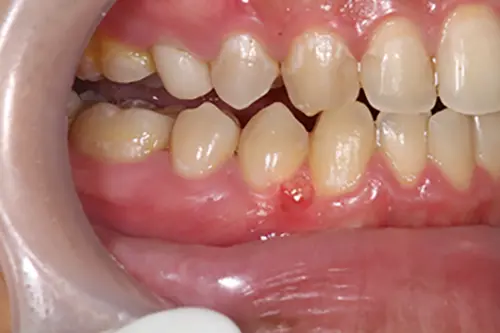

これって大丈夫?歯茎にできる口内炎アップル歯科伊丹駅前。